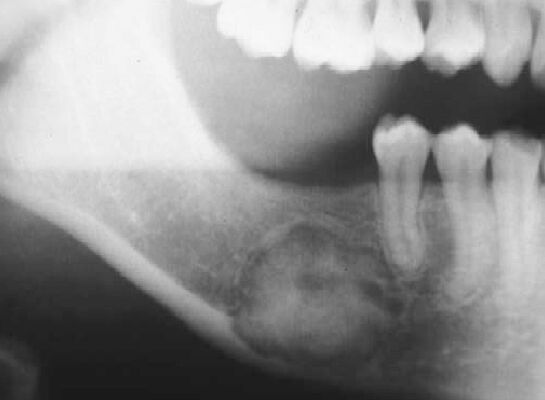

66.17歲男孩因上顎右側有一個無疼痛的腫脹而來求診,經X光檢查(如附圖)發現一個放射線不透過性影像如 箭頭所示之區域,根尖片可見到此病變與周圍界線不清楚,此病患最可能罹患下列何種疾病?

(A)家族性巨大畸形牙骨質瘤(familial gigantiform cementoma)

(B)繁盛性牙骨質骨發育不良(florid cemento-osseous dysplasia)

(C)纖維性發育不良(fibrous dysplasia)

(D)骨化纖維瘤(ossifying fibroma)

B)通常雙側、多處發生,可能會吃穿mucosa露出cemento-like的物質,PANO 初期看起來有點像periapical cyst後期RL的病灶中會包著RO(跟periapical cemento-osseous dysplasia一樣),不會造成bony expansion

D)好發於中年女性下顎後牙區,界限明確,中間出現鈣化組織(unilocular mixed RO/RL),可能會造成bony expansion